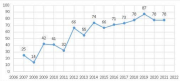

| 04:29, 17 בספטמבר 2023 | מלנומה בעולם9.png (קובץ) |  |

50 קילו־בייטים | Motyk | 1 | |

| 04:27, 17 בספטמבר 2023 | מלנומה בעולם.png (קובץ) |  |

51 קילו־בייטים | Motyk | 1 | |

| 19:53, 16 בספטמבר 2023 | מלנומה יהודים 7.png (קובץ) |  |

49 קילו־בייטים | Motyk | 1 | |

| 19:43, 16 בספטמבר 2023 | מלנומה יהודים6.png (קובץ) |  |

93 קילו־בייטים | Motyk | 1 | |

| 19:36, 16 בספטמבר 2023 | מלנומה יהודים 3.png (קובץ) |  |

53 קילו־בייטים | Motyk | 1 | |

| 18:11, 16 בספטמבר 2023 | מלנומה יהודים2.png (קובץ) |  |

71 קילו־בייטים | Motyk | 1 |